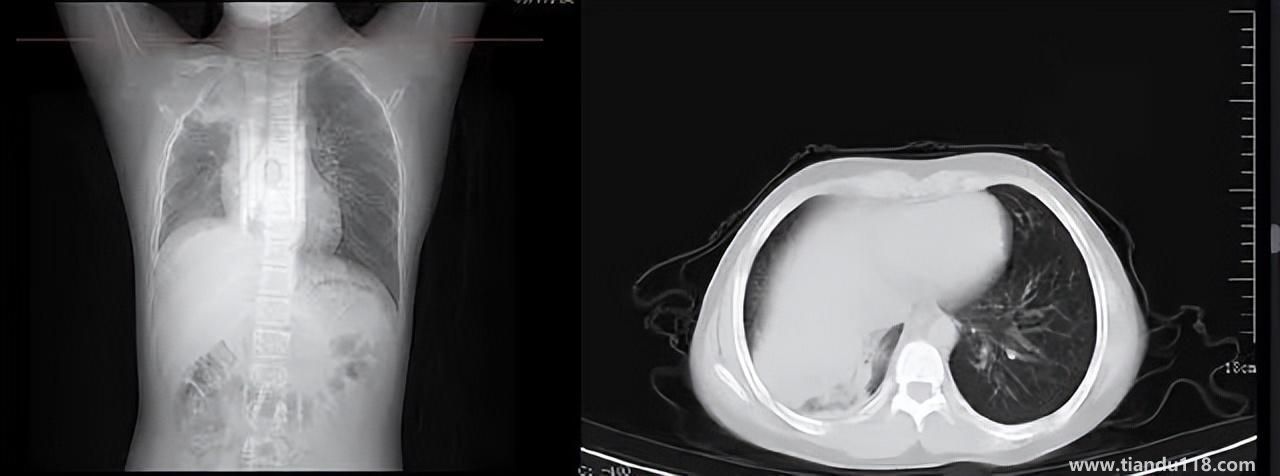

男孩咳嗽發(fā)熱在家硬扛成白肺(醫(yī)生表示以下幾種情況別硬“扛”) 男孩咳嗽發(fā)熱在家硬扛成白肺(醫(yī)生表示以下幾種情況別硬“扛”) 近日,一名12歲男孩咳嗽一周不就醫(yī),一側(cè)肺部“扛”成了“白肺”?!氨е鴥e幸心理一直在家硬‘扛’,沒(méi)想到‘扛’出這么重的??!”孩子家長(zhǎng)悔不... 小編 2022-12-28 939

感染新冠會(huì)變白肺?醫(yī)生:有年輕病例 感染新冠會(huì)變白肺?醫(yī)生:有年輕病例感染新冠會(huì)變白肺嗎?對(duì)此,有專(zhuān)家表示,造成“白肺”情況有很多種,感染新冠只是一種可能。少量患者肺有滲液 ,咳嗽不會(huì)引發(fā)白肺,有年輕人病例。... 小編 2022-12-27 608

3個(gè)辦法可提前預(yù)警白肺(咋預(yù)防“白肺”) 3個(gè)辦法可提前預(yù)警白肺(咋預(yù)防“白肺”)家里有老人,擔(dān)心出現(xiàn)“大白肺”、“沉默型缺氧”等情況,具體如何應(yīng)對(duì),提前預(yù)警?近日,大象新聞接到諸多咨詢(xún)。針對(duì)這些問(wèn)題,大象新聞?dòng)浾咦隽硕喾讲稍L。什么是白肺?對(duì)... 小編 2022-12-28 693

為何有人出現(xiàn)“白肺”?專(zhuān)家回應(yīng)和疫苗接種無(wú)關(guān) 為何有人出現(xiàn)“白肺”?專(zhuān)家回應(yīng)和疫苗接種無(wú)關(guān)國(guó)務(wù)院聯(lián)防聯(lián)控機(jī)制12月27日召開(kāi)新聞發(fā)布會(huì),針對(duì)有媒體提問(wèn)稱(chēng),從近期公眾的反映情況看,有的新冠病毒感染者在就診過(guò)程中發(fā)現(xiàn)了肺炎或者是CT出現(xiàn)了“白肺”的現(xiàn)... 小編 2022-12-27 817